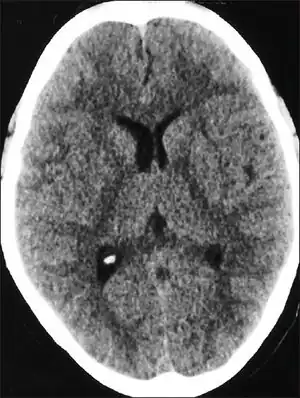

| CT scan of the head showing diffuse effacement of cerebral sulci and compression of the ventricles in a case with high altitude cerebral edema[1] | |

People with HACE have an elevated white blood cell count, but otherwise their blood count and biochemistry are normal. If a lumbar puncture is performed, it will show normal cerebral spinal fluid and cell counts but an increase in pressure.[10] In one study, CT scans of patients with HACE exhibited ventricle compression and low density in the cerebellum.[10] Only a few autopsies have been performed on fatal cases of HACE;[11] they showed swollen gyri, spongiosis of white matter, and compressed sulci. There was some variation between individuals, and the results may not be typical of HACE deaths.[11]

Recovery varies between days and weeks,[11] but most recover in a few days.[28] After the condition is successfully treated, it is possible for climbers to reascend. Dexamethesone should be discontinued, but continual acetazolamide is recommended.[32] In one study, it took patients between one week and one month to display a normal CT scan after suffering from HACE.[10]